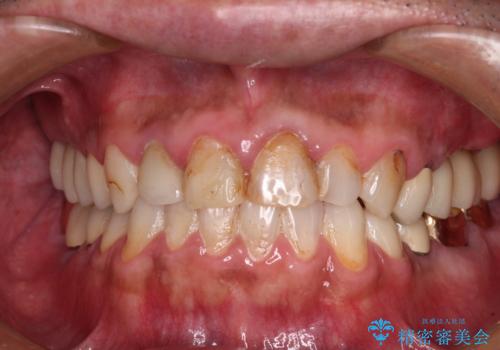

かぶせものと歯ぐきの境目が黒い 40代女性

保険のかぶせ物・詰め物を金属を使わないセラミックへ 自然な見た目へ